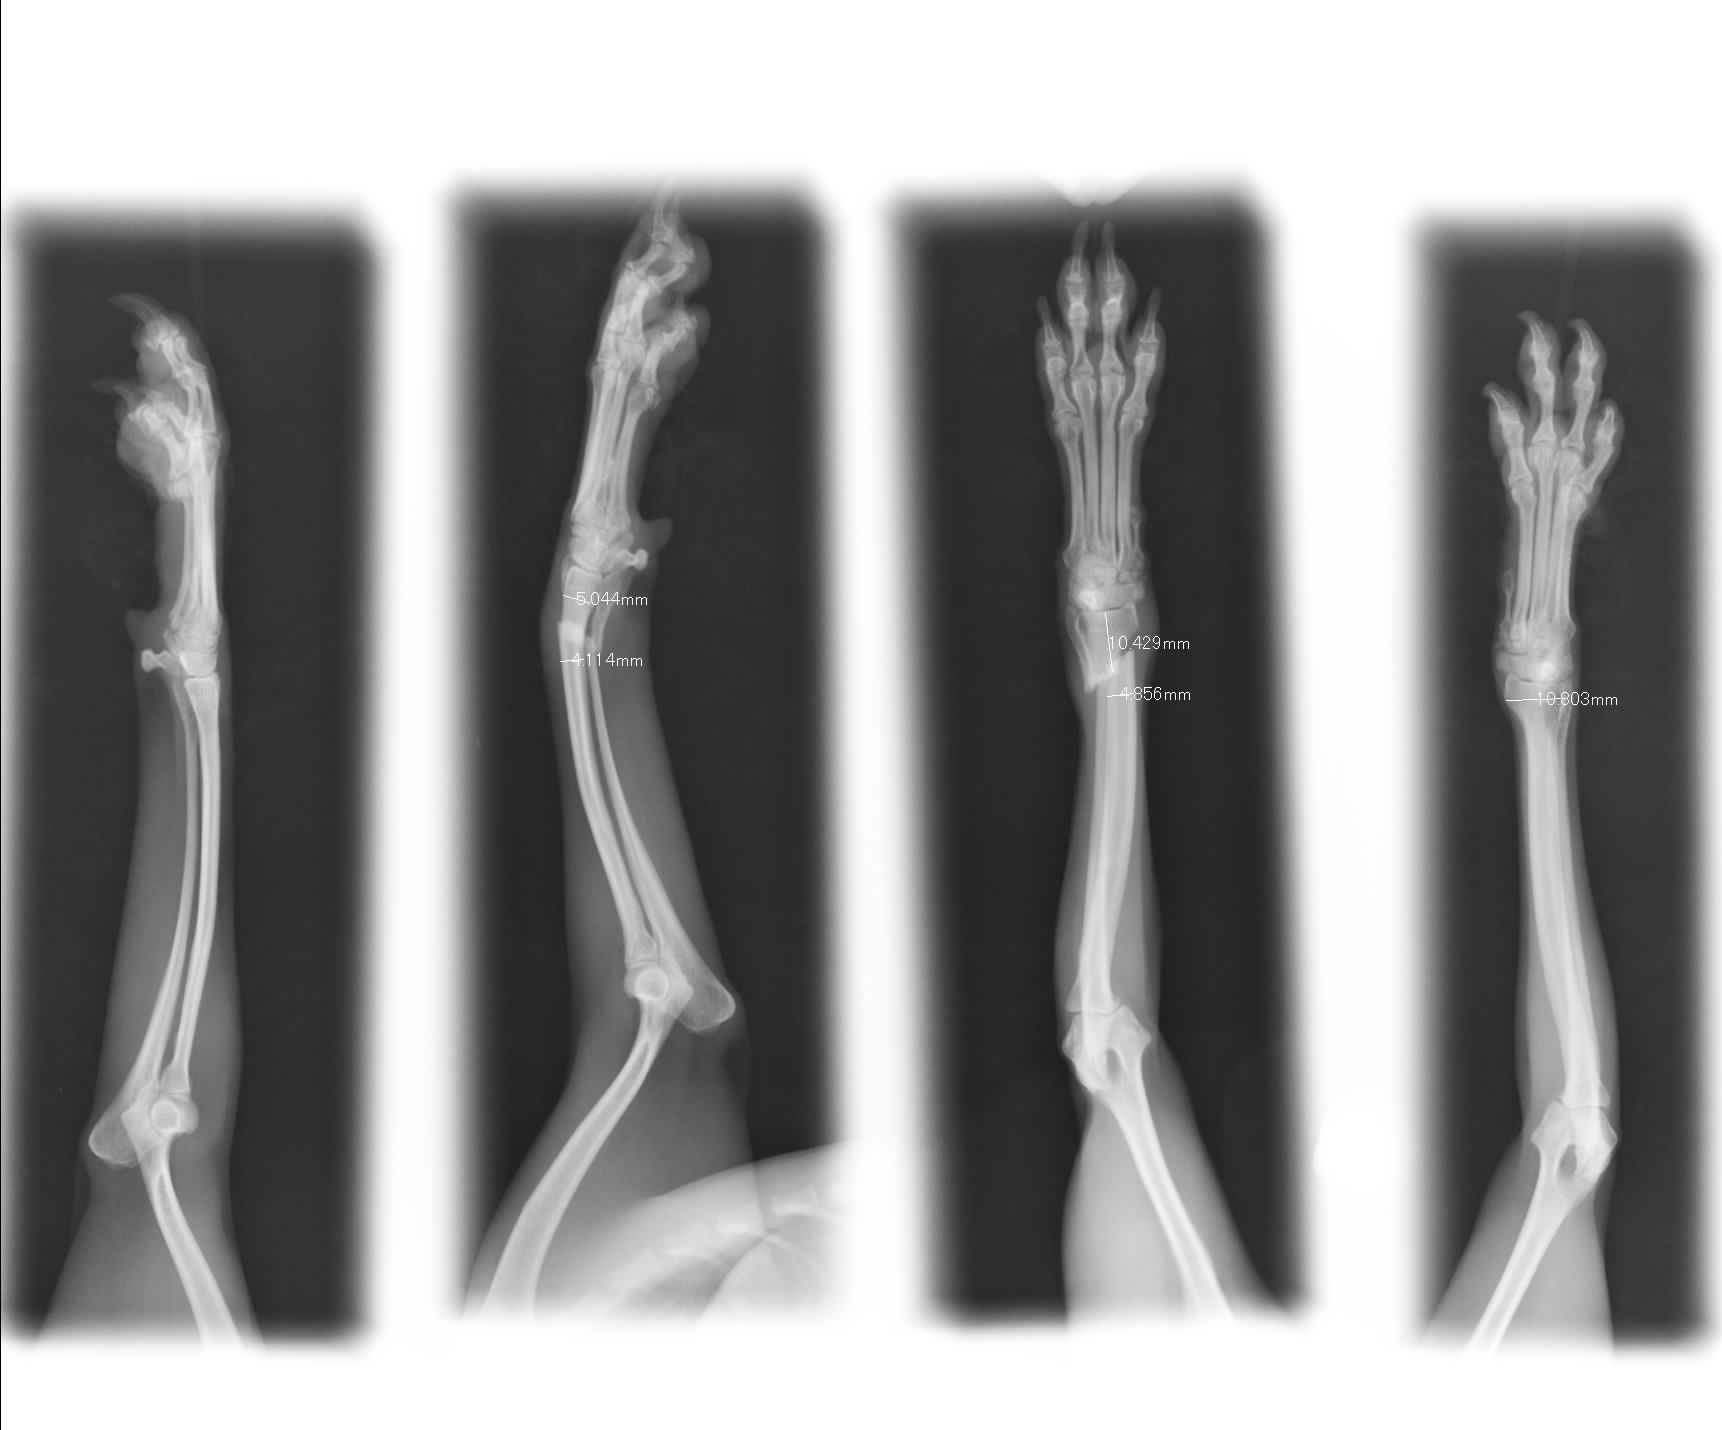

ソファーの上り下りで肢を痛めました、T.プードル1歳のももちゃんです。

尋常じゃない痛がりかた。

レントゲンを撮影しますと・・・

次の日に手術です

長い時間かけてプレートを入れました。

1ヶ月後に1枚プレート抜く予定です。

4~5mm幅の骨です。

スクリューは1~1.5mmの使用です。

細かすぎて・・・

ジャンプに注意して下さい。